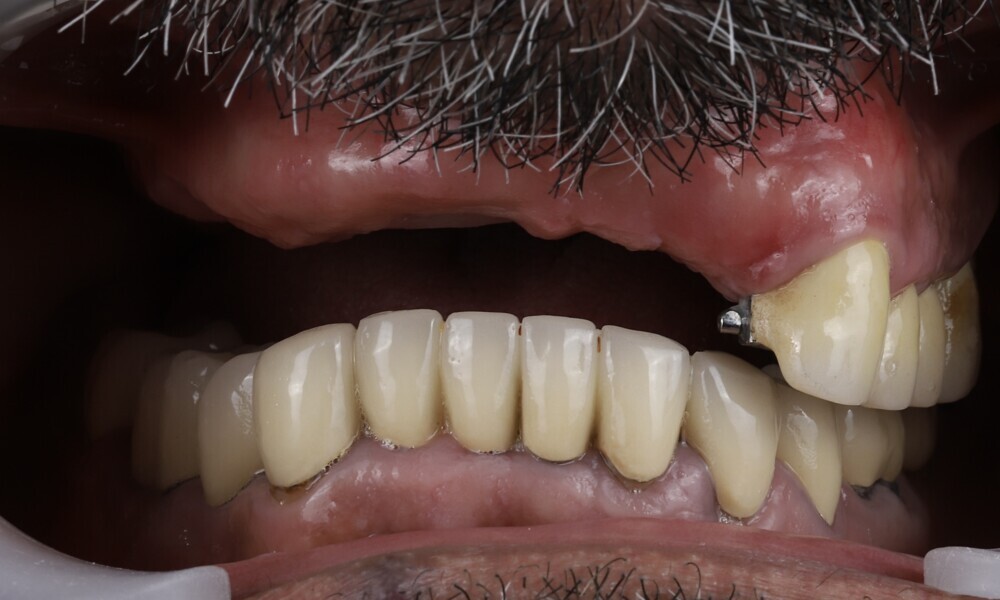

Employing a fully guided surgical protocol alongside a completely digital prosthetic workflow allowed for the precise design and milling of a PMMA provisional prosthesis (Figs. 34 & 35). The implant loading protocol implemented was immediate loading with equal distribution of forces across the entire prosthesis. The patient received the screw-retained provisional prosthesis on the same day. Temporary abutments (titanium copings) were placed on top of the screw-retained abutments. The spaces between the titanium copings and the provisional prosthesis were filled (Figs. 36–38). Any excess material was cut away, and the provisional prosthesis was subsequently polished to ensure a smooth finish (Fig. 39). The provisional prosthesis was then attached and securely fixed to the titanium copings to a 15 N cm torque (Fig. 40). Oral hygiene instructions were provided, and the occlusion was assessed (Figs. 41 & 42). A final control radiograph was obtained and confirmed that all parameters were within normal limits (Fig. 43).

During follow-up visits, the patient exhibited excellent healing and no postoperative complications (Fig. 44). The provisional prosthesis demonstrated optimal fit and stability, enhancing function and the patient’s comfort.